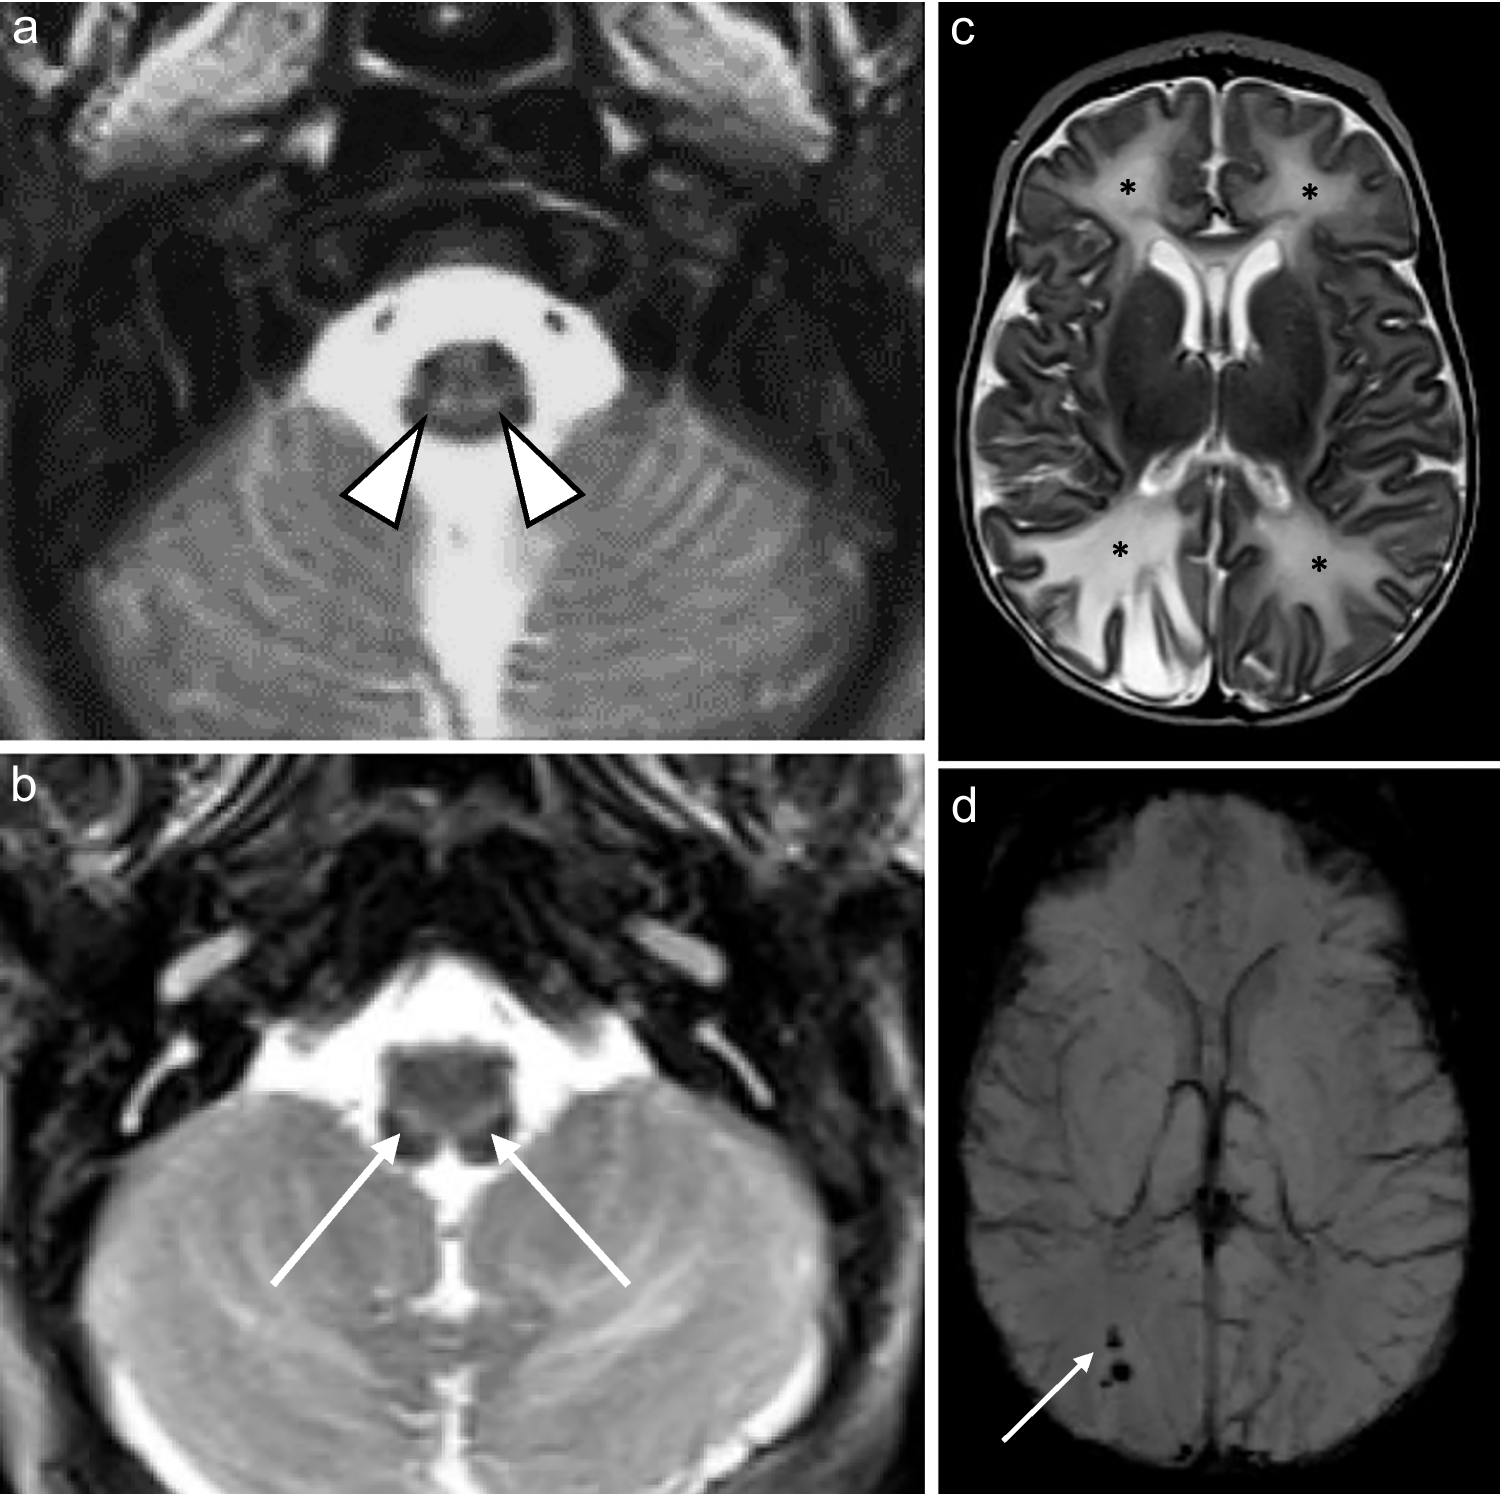

Fig. 1

An 11-day-old boy with genetically confirmed MPV17-related mitochondrial depletion syndrome. a Axial T2-weighted image shows hyperintense signal in the reticulospinal tracts of the proximal cervical cord (arrowheads). b Axial T2-weighted image shows hyperintense signal in the reticular formation in the medulla (arrows). c Axial diffusion-weighted image and (d) apparent diffusion coefficient map demonstrate restricted diffusion in the perirolandic cortex (arrows)

Perirolandic cortex

Signal alterations in the sensorimotor cortex were identified in the two neonates (Figs. 1 and 2). This was differentiated from hypoxic ischaemic injury based on clinical histories which excluded perinatal asphyxia, the absence of characteristic changes in the basal ganglia-thalamus complex (posterolateral putamina and ventrolateral thalami), and the presence of restricted diffusion which would confine any potential hypoxic ischaemic injury to the acute phase. Perirolandic signal abnormality did not extend into the paracentral lobule [13].